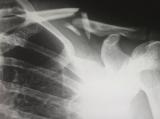

В МЦ ЭРЕБУНИ проведена уникальная операция на позвоночнике. После аварии у молодого человека произошел вывих первого и второго шейных позвонков со значительным смещением. Помимо этого, был серьезный перелом второго...